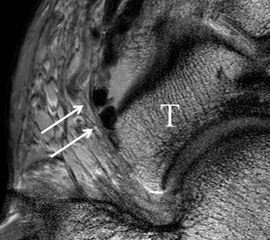

Der Ursprung des Ligamentum fibulocalcaneare liegt unmittelbar kaudal und dorsal des Ursprungs des Ligamentum fibulotalare anterius, so dass gehäuft kombinierte Verletzungen und auch ein gemeinsamer knöcherner Ausriss beobachtet werden. Nach kaudal dorsal verläuft das Band dann nach medial konvex unter die Peroneussehnen. Danach ist ein schräg deszendierender, gestreckter Verlauf bis zum calcanearen Ansatz abgrenzbar (Abb. 10). Dieser zu allen drei Standardebenen schräge Verlauf erschwert häufig die Diagnostik des LFC vor allem bei subtileren Verletzungen. Spezialprojektionen, die dem Bandverlauf orthograd folgen (entweder schräg coronar oder schräg sagittal) erleichtern auch hier die Diagnostik (Abb. 11) insbesondere nicht dislozierter Avulsionen. Assoziierte Verletzungen der Peroneussehnenloge müssen mit beurteilt werden, wobei neben Verletzungen der Sehnen und Sehnenscheiden die Beurteilung des Retinaculum peroneum superius und inferius wichtig ist. In einem Kollektiv von Patienten mit chronischen Außenbandinstabilitäten weisen 50% der Patienten eine Verletzung dieser Strukturen auf 5. Auch hier erleichtern hochauflösende Techniken die Diagnostik (Abb. 12).